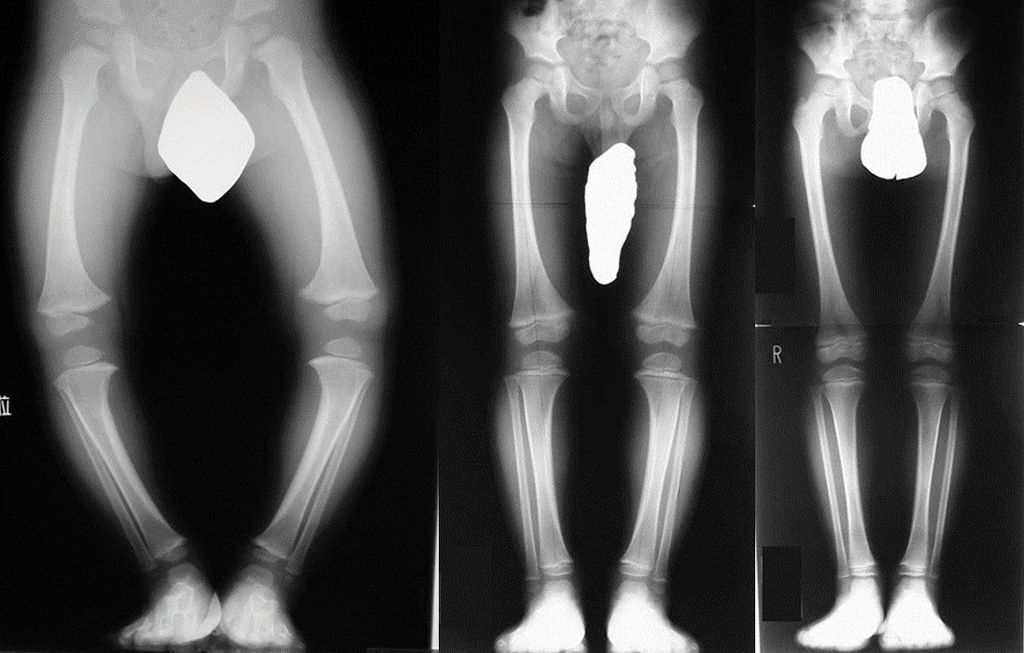

跛行 こどもの跛行(はこう)って? 成長痛 こどもが脚を痛がる 斜頸~赤ちゃん編~ 赤ちゃん、こどもの首が傾いている? 股関節脱臼 赤ちゃんは教えてくれない!? О脚 こどものО脚について知ろう 内反足 赤ちゃんの足、曲がっていませんか? 1